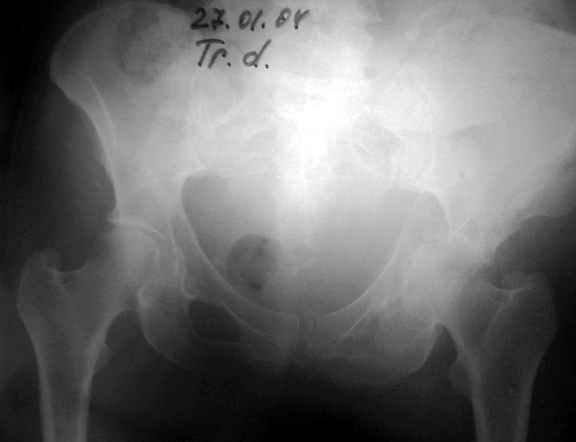

Диагноз- перелом с вовлечением таза, разрыв правого сакро-илиак сочленения vertical shear injury, перелом крыла подвздошной кости?, перелом ацетабулум Т type или Both column?, перелом шейки бедра, перелом проксимального отдела бедра.

перелом крыла правой подвздошной кости, перелом обеих колонн вертлужной впадины, двусторонний перелом лонных костей (С2.2) повреждение передних связок правого крестцово-подвздошного сочленения,

ипсилатеральный перелом шейки и диафиза бедра.

27.01.04